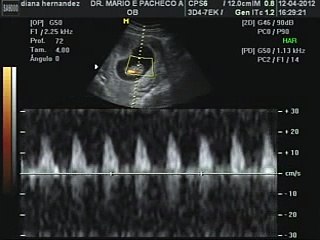

hola hace 15 días me hicieron mi primera ecografia y tenia 6 semanas de embarazo y salio el embrión pero no se veía latido cardíaco fui donde mi medico de cabecera y me dijo que era muy rápido para verlo, que esperara dos semanas mas y ya este lunes 17 me hice otra ecografia y el mismo cuento no se ve el latido de mi bebe ya tengo 8 semanas pero vi a mi bebe mas Ultrasonido con transductor endovaginal Dentro del útero se observa un feto rodeado por liquido amniótico, cuya longitud cráneocaudal (CRL) mide 27cm, que corresponde a 9 semanas y 4 días de embarazo Se distinguen la cabeza, el tronco y los esbozos de bazos y piernas Durante el estudio se pueden registrar movimientos corporales y elE l ultrasonido usa ondas sonoras que producen una imagen del interior de una parte de su cuerpo El ultrasonido se usa durante el embarazo para monitorear el crecimiento de su bebé y detectar anormalidades físicas Usted se reunirá con el obstetra o el auxiliar de ecografía que llevará a cabo el procedimiento para discutir su tratamiento

Ultrasonido bebe de dos semanas de gestacion- La ecografía que se suele hacer en la semana 6 de embarazo es un ultrasonido transvaginal que permite ver la cámara gestacional Esta es una estructura negra con forma algo ovalada que tiene un círculo blanco, es decir, una estructura que sirve para alimentar al embrión durante las primeras etapas de embarazo Con la ecografía podremos observar al embrión, pero veremos queEl ultrasonido obstétrico es un examen clínico que resulta útil para establecer la presencia de un embrión / feto con vida estimar el tiempo de gestación del embarazo diagnosticar anormalidades congénitas del feto evaluar la posición del feto evaluar la posición de la placenta determinar si el embarazo es múltiple

Según el Congreso Americano de Obstetras y Ginecólogos (ACOG, por siglas en inglés) a las 4 ó 5 semanas de embarazo, el ultrasonido debe ver un saco gestacional, la estructura donde crecerá el bebé Antes de este tiempo es muy posible que no se vea el embrión Si el ultrasonido se hace alrededor de las 6 ó 7 semanas y no se ve al bebé Tercer ultrasonido se realiza en la semana 3334 En esta etapa de embarazo se mide el peso fetal y aquí es donde se conoce si está creciendo a un ritmo;Ultrasonido de bebe de 15 semanas de gestacíon que abre la boca